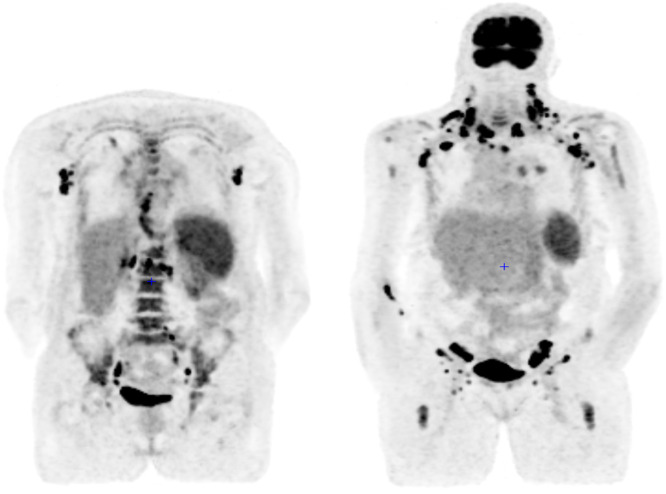

We describe the case of a female patient with May-Hegglin syndrome who developed peripheral T-cell lymphoma not otherwise specified. The patient presents with systemic lupus erythematous phenotype and myelofibrosis secondary to T-cell lymphoma. Peripheral T-cell lymphoma not otherwise specified, represents 25 % of all peripheral T-cell lymphoma. Its diagnosis remains challenging due to the polymorphous clinical presentation and pathological heterogeneity. Myelofibrosis associated with malignant lymphomas is rare and peripheral T-cell lymphoma is even rarer. To our knowledge, this is the first case to describe an association between May-Hegglin syndrome and a peripheral T-cell lymphoma.